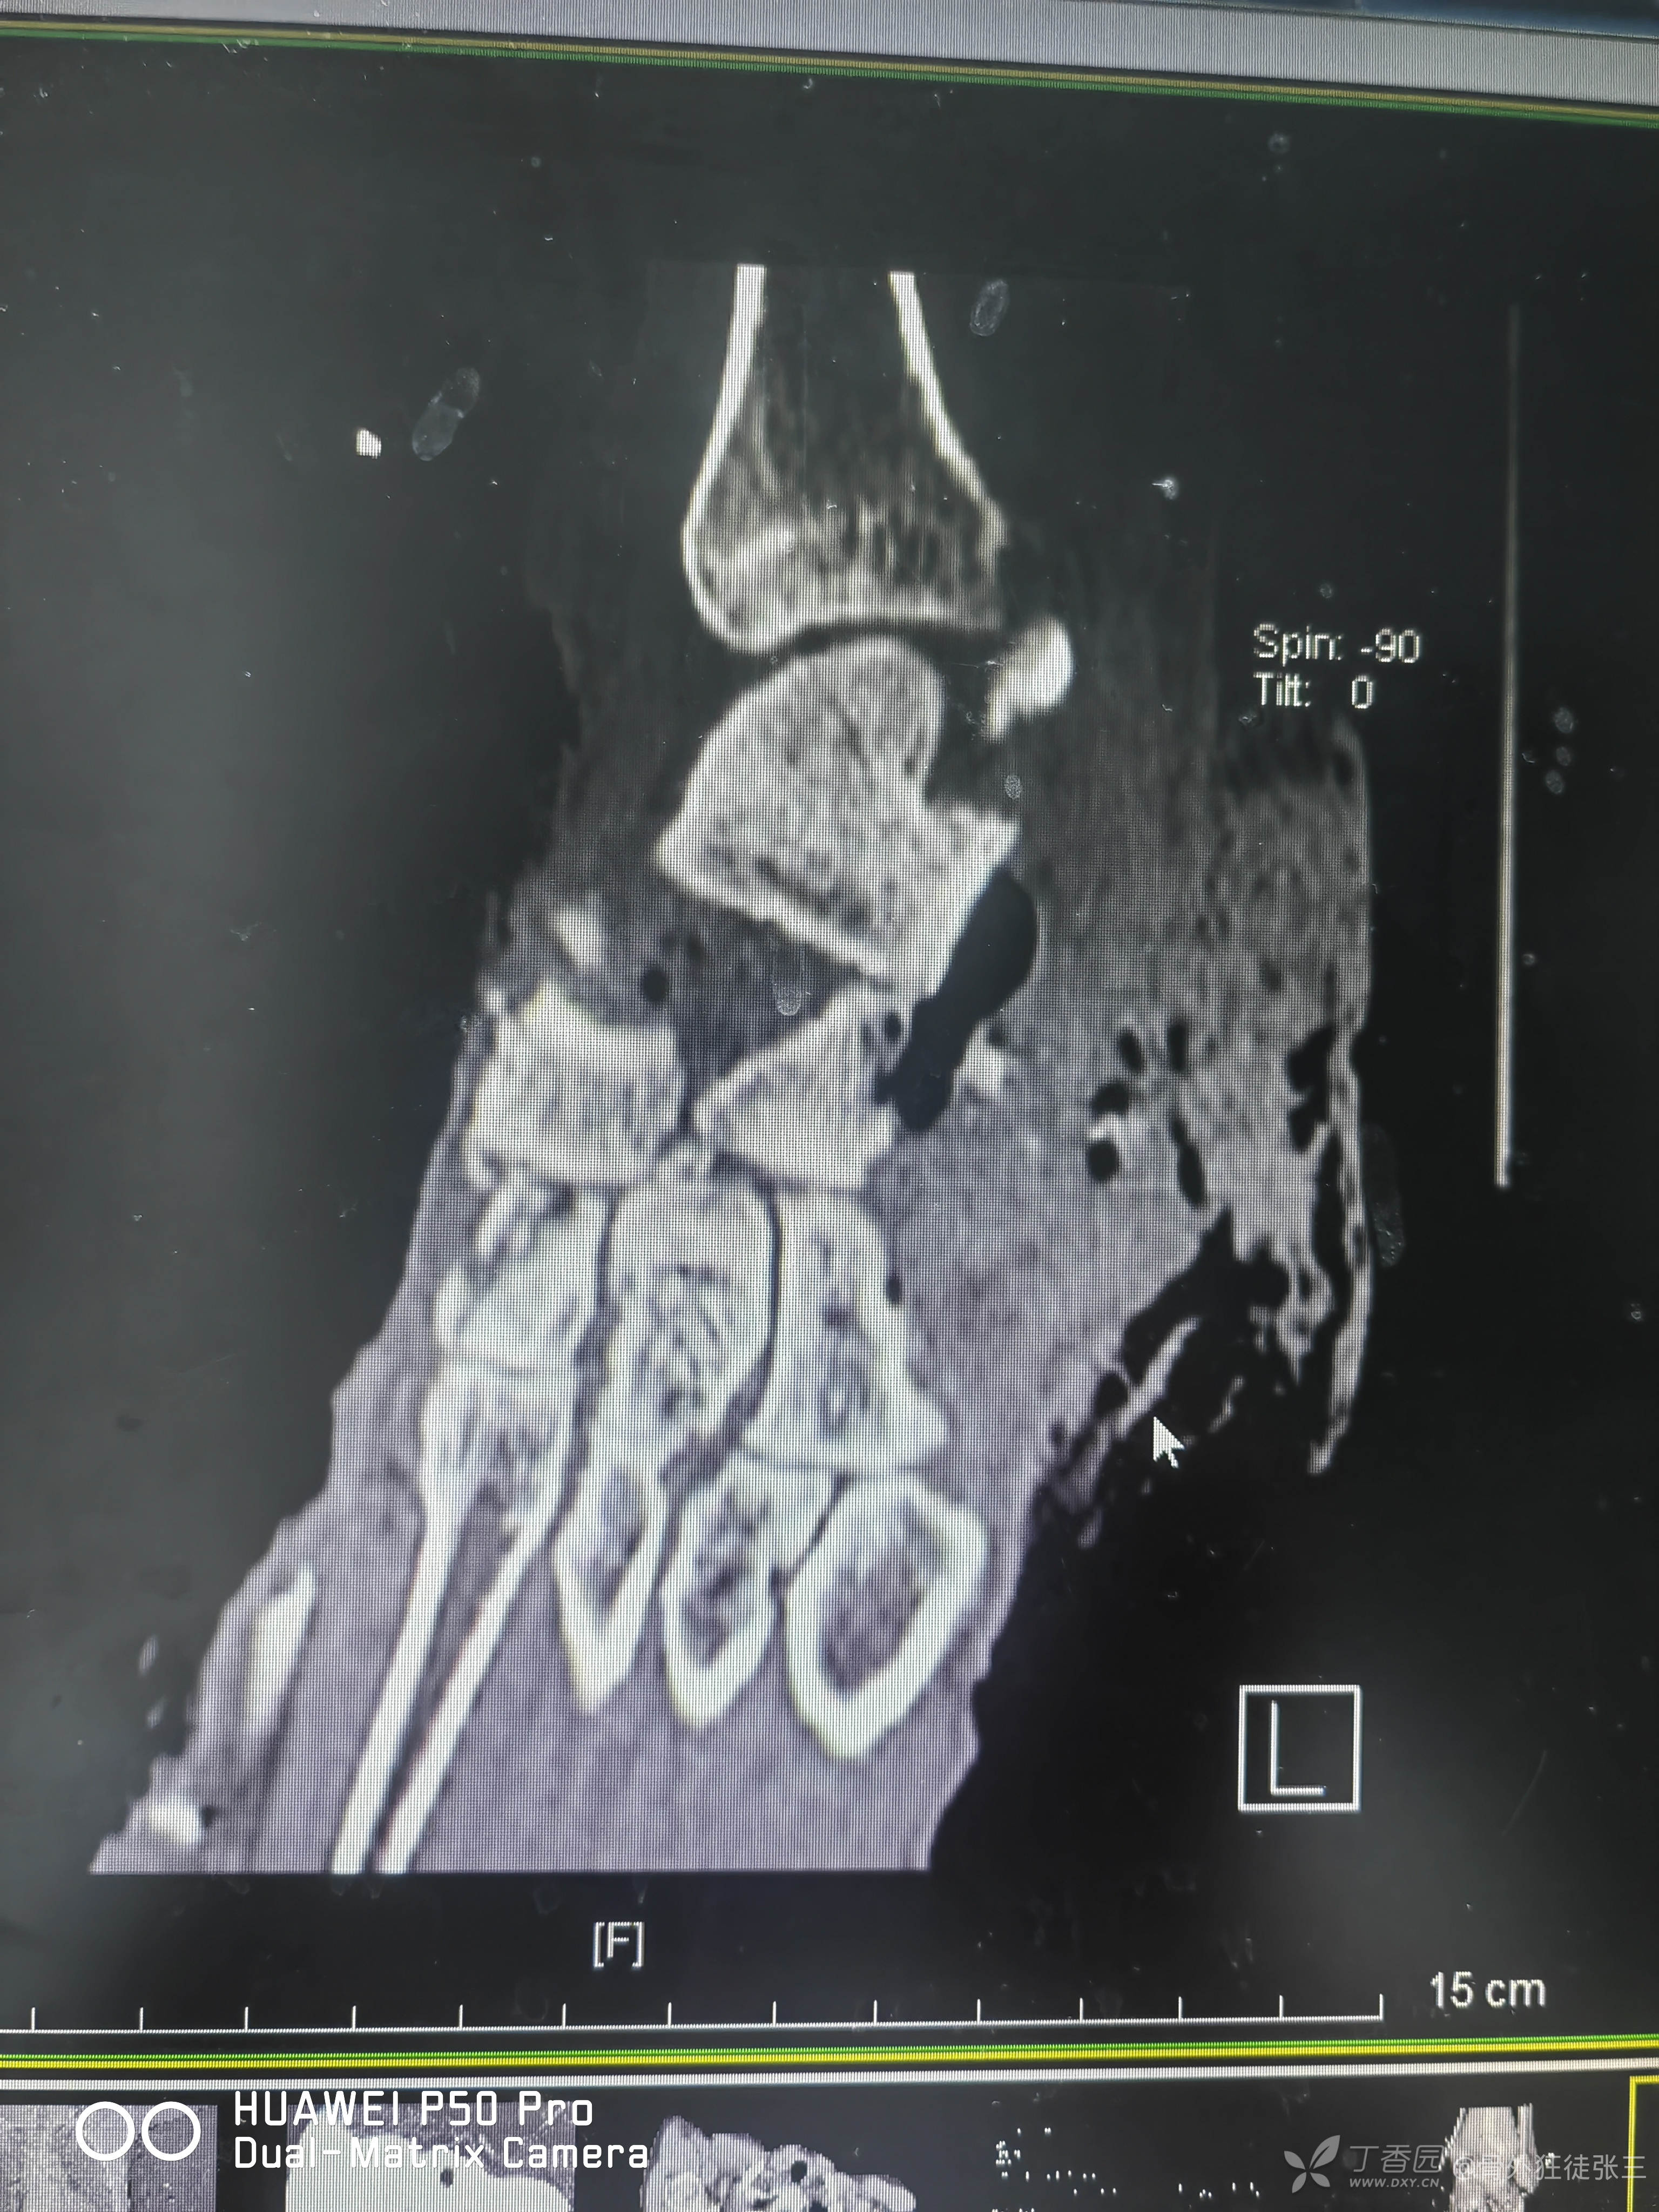

目前的影像学

第一跖骨骨缺损处为抗生素骨水泥